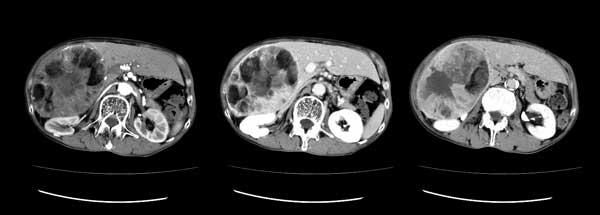

脂肪肝とは?CT,MRI画像診断のポイントは。